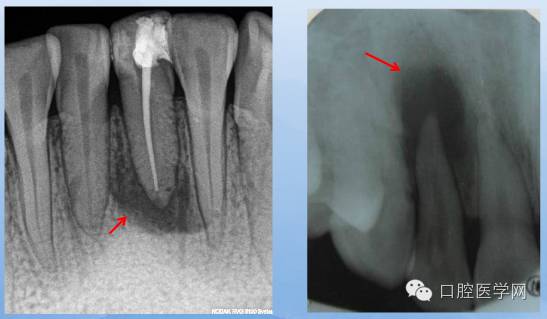

X线表现:根尖部不规则,小区域的透射影,边界不整齐,范围局限。

X线表现:根尖区边界不清楚但不锐利的透射区,密度不规则。

X线表现:范围较小,周界清晰,无致密骨壁线。

X线表现:可见病原牙,透射区边界清晰锐利,边缘有致密的骨硬板。